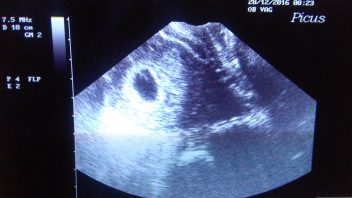

Měly by. Dnes jsem totiž zjistila, že čekáme novoroční miminko. Blbě už mi je týden. Bolel mě podbřišek, ale protože jsme tenhle měsíc neměli moc příležitostí provozovat lásku a oba termíny, kdy jsem si myslela, že mám ovulaci jsme propásli, moc šancí jsem tomu nedávala. A ono hele, jsou tam, slabé, tiché ale jsou. Nemohla jsem věřit svým očím a pořád se chodím koukat na ten malý proužek papíru a ujišťuji se, že tam jsou obě dvě. Muž mě zase straší dvojčaty. 🙂 Ale ať je jedno nebo dvě hlavně ať se do pelíšku pěkně zavrtá a zůstane tam až do konce.